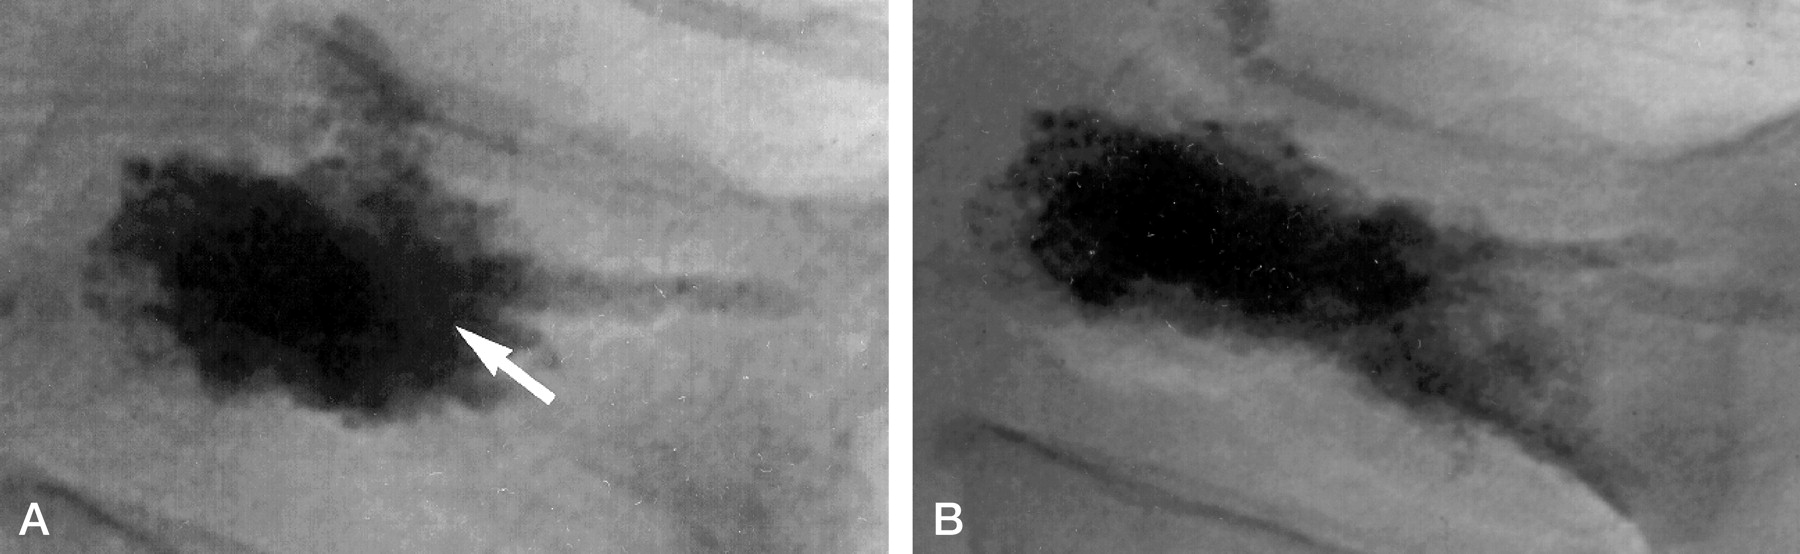

76-year-old man with L1 vertebral body fracture.

A, Lateral conventional radiograph after initial vertebroplasty. After administration of 3 mL of cement via a left unilateral transpediculate approach, the cement opacifies the anterior portion of the vertebral body (arrow). The patient reported complete pain relief after the procedure.

B, Lateral conventional radiograph after repeat vertebroplasty. After administration of an additional 1.2 mL of cement via a right unilateral transpediculate approach, the filling pattern has changed from A to include prominent posterior opacification. The patient reported moderate pain relief after the procedure.

After undergoing a screening and preprocedural workup, as described by Jensen et al (9), he underwent a percutaneous vertebroplasty procedure, performed as described by Kim et al (10). Using a left unilateral transpediculate approach, the operator injected 3 mL of PMMA cement and noted an opacification pattern that filled both hemivertebrae, as seen on an anteroposterior radiograph, and filled predominantly the anterior half of the vertebral body, as seen on a lateral radiograph (Figure 1A). Preoperatively, the patient reported pain of 10/10 in severity, with mobility restricted to the use of a walker to assist with ambulating. At 1 week postoperatively, however, he reported complete pain relief (0/10 in severity), with no restriction of mobility.

At that time, he was referred to our institution again for evaluation for candidacy for percutaneous vertebroplasty. Despite the absence of new radiologic findings, we opted to re-treat the L1 vertebral body on the basis of the patient’s medical history and physical findings. The procedure was again performed as described by Kim et al (10), this time by using a right transpediculate approach with the injection of 1.2 mL of PMMA cement. The cement-filling pattern visualized on a lateral radiograph changed from the initial procedure to include prominent posterior opacification (Figure 1B). The patient also received left L3–L4 and left L4–L5 facet injections to alleviate the left hip pain because of the findings on a previous bone scan demonstrating increased uptake of radiotracer at the facets at those levels. Preoperatively, the patient reported pain of 10/10 in severity, with mobility restricted to sitting in bed. At 1 week postoperatively, however, he reported moderate pain relief, with a reduction in pain to 6/10 in severity, and his only restriction in mobility was the use of a walker to assist in ambulating.